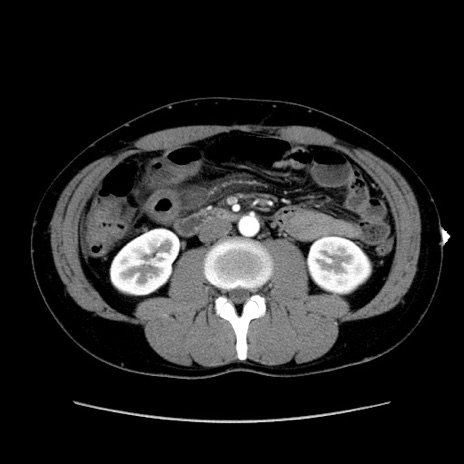

症例36(横断像)

【症例】20歳代 男性

【主訴】心窩部痛

【現病歴】今朝より上腹部痛あり。一旦軽快していたが再度出現したため救急要請。昨日夕に白身の魚を含む刺身を食べた。

【身体所見】BP 136/89mmHg、HR 74/min、BT 37.0℃、腹部:膨満、軟、心窩部に圧痛あり。反跳痛なし、筋性防御なし、腸雑音やや亢進あり。

【データ】WBC 17700、CRP 0.48